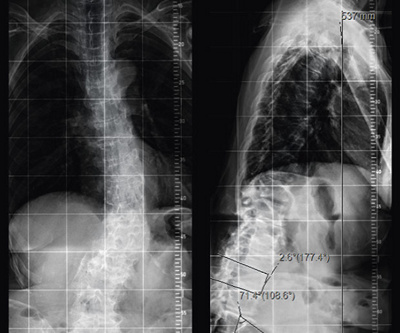

Wenn alle diese Massnahmen nicht ausreichen, besteht die Möglichkeit einer Operation. In der Regel sind grössere Operationen notwendig, um den Rücken in ein gutes Gleichgewicht zu bringen. Versteifungen des Rückens sind dabei meist nicht zu vermeiden, so dass eine Einschränkung der Beweglichkeit die Folge ist (Abb. 2 und 3).

Abb. 2

Röntgenbilder von vorn (links) und von der Seite, 78-jährige Patientin mit schwerer Fehlhaltung vor der Operation

Abb. 3

Röntgenbilder derselben Patientin nach der Operation